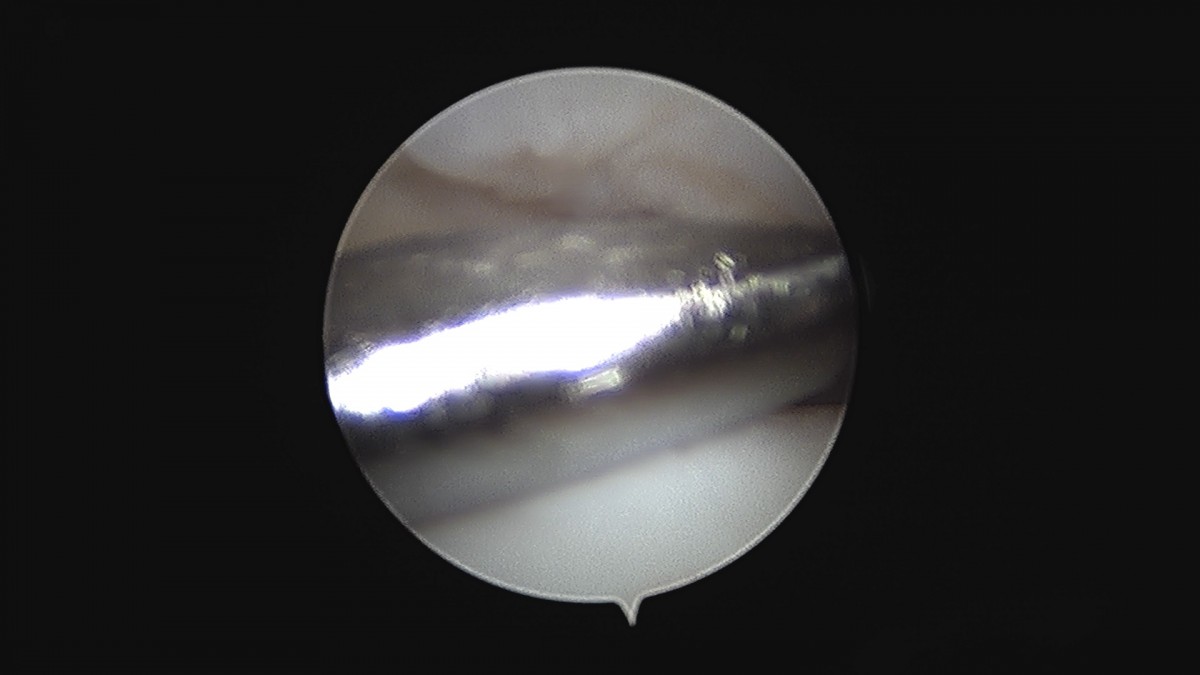

이재상원장님 무릎 변연절제술 권오O 환자

작성자 최고관리자 댓글 0건 조회 373회 작성일 25-09-16 16:11